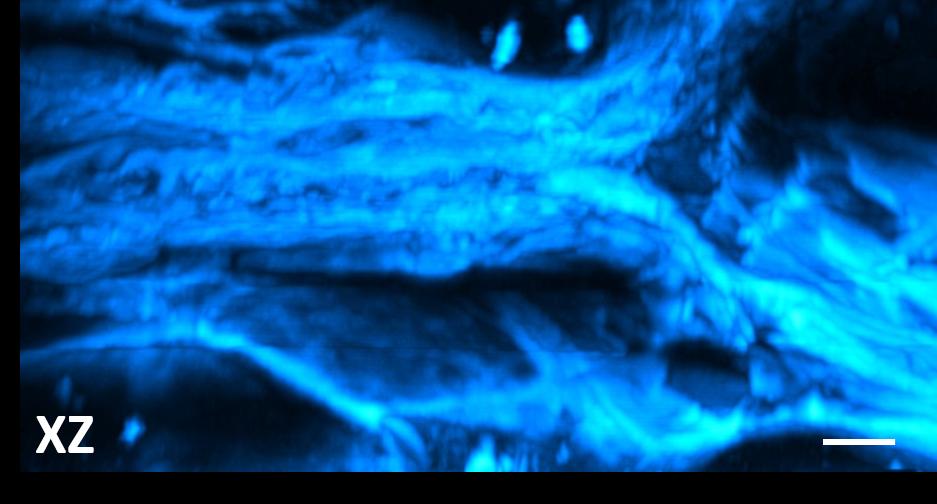

Mit der Third Harmonic Generation als Kontrastmechanismus lassen sich besonders gut Grenzschichten, z. B. Abgrenzungen von Fetttröpfchen oder -gewebe abbilden. Dies ist besonders interessant, wenn der Fettstoffwechsel in Organismen oder menschlichen Gewebe untersucht werden soll. Wie schon bei der SHG werden für diese Methode keinerlei Fluoreszenzfarbstoffe und keine möglicherweise störende Färbung benötigt.

Aufgrund der verwendeten Wellenlängen im Nahinfrarot-Bereich eignet sich diese Methode besonders gut für die dreidimensionale Bildgebung in stark streuuendem Gewebe.

3D-Schnitt mit THG von Fettgewebe der Maus. Skalierung 10 µm